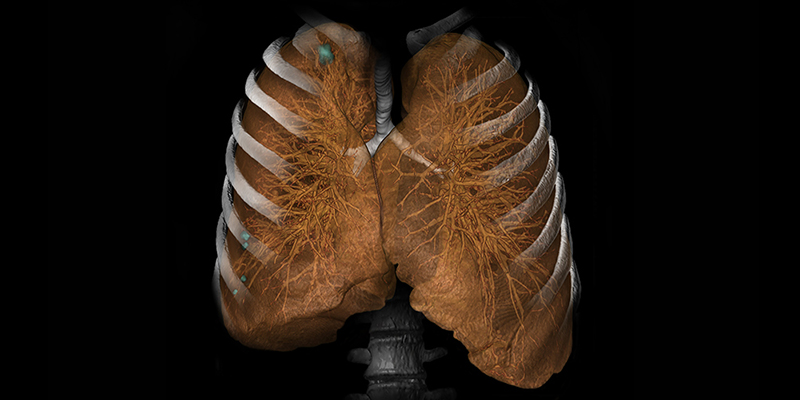

Програмний пакет MR Neuro

Опції експертного рівня для аналізу даних МРТ у пацієнтів з підозрою на інсульт дозволяють повністю автоматизувати процес і економити час. Найсучасніші програми надають користувачам новітні інструменти та програми для нейровізуалізації.